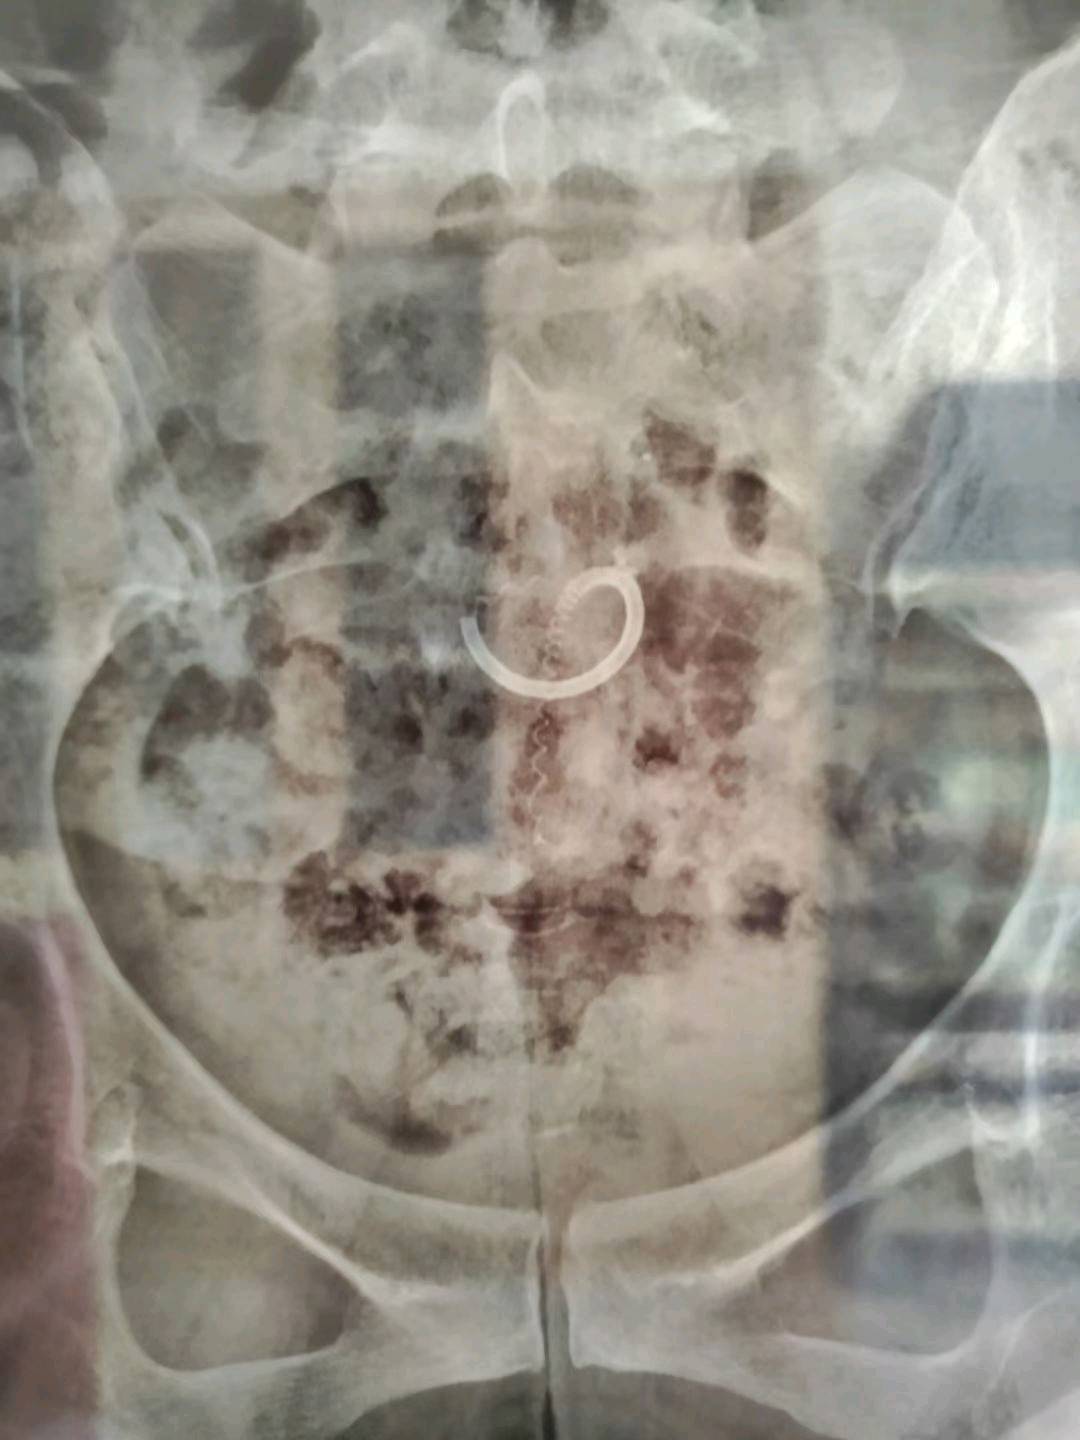

患者45岁,G1P2,剖宫产双胎1次(自然妊娠)。安环23年,异常子宫出血月经淋漓不尽2个月,外院取环残留,环断裂,外院医生述取出约10cm变形环段,腹部平片见O型环断裂,断端指向宫颈管。宫颈位于前穹隆顶端,暴露困难,艰难置入宫腔镜,见内膜杂乱,反复寻找才发现O型环残环,残环两侧与宫壁嵌顿,异物钳抓取数次均滑脱,顺宫颈管向下寻找,在宫颈管中上段找到环断端,异物钳缓慢拉出断端至宫颈外口,中弯钳配合卵圆钳牵拉,环断裂,取出约10cm环残段。宫腔镜再次进入宫腔,找到剩余残环,异物钳夹取,多次滑脱,取环钩顺着镜鞘外侧进入宫腔,钩住残环,缓慢下拉至宫颈外口,中弯钳配合卵圆钳拉出约12cm环残段,宫腔镜再次探查宫腔,镜下未见环残留,取内膜送病检。术后病人离院时复查B超,有强回声带,因宫腔少许气体干扰,无法确定是否环残留,嘱病人一周后复查B超,确定无环残留。第一次遇到这么脆弱的金属圆环,很容易断裂。病检为子宫内膜增生,不伴非典型增生。